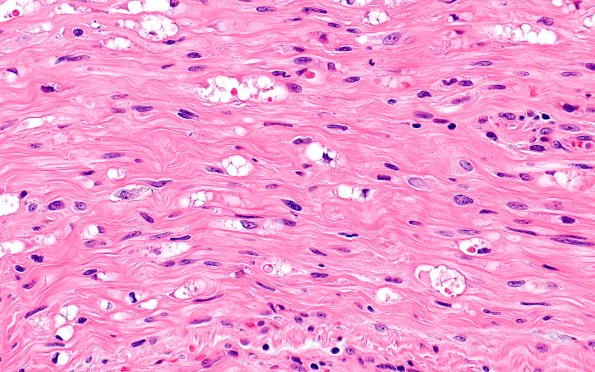

Washington University Experience | PERIPHERAL NEUROPATHY | 4 AXONAL DEGENERATION | 1 H&E & IHC | 3A3 Axonal Degeneration (Case 3) H&E 40X

This is a longitudinal section of one nerve fascicle showing degenerating globular debris consistent with surgical trauma from the original tumor resection. Some fascicles (not shown) show nearly normal axonal preservation (H&E)